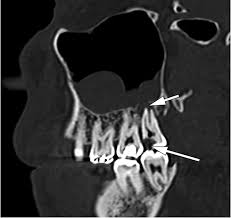

الاضراس السفلية تكون في بعض الاحيان قيبة جدا ومتداخل مع قناة العصب السنخي

الاضراس العليا تكون احيانا في وضع قريب جدا من الجيوب في الفك العلوي واحيانا تكون ملاصقة

قدر هذه المريضة ان اضراس العقل السفلية قريبة جدا من مجرى العصب السنخي

واضراس العقل العليا قريبة جدا من جيوب الفك العلوي